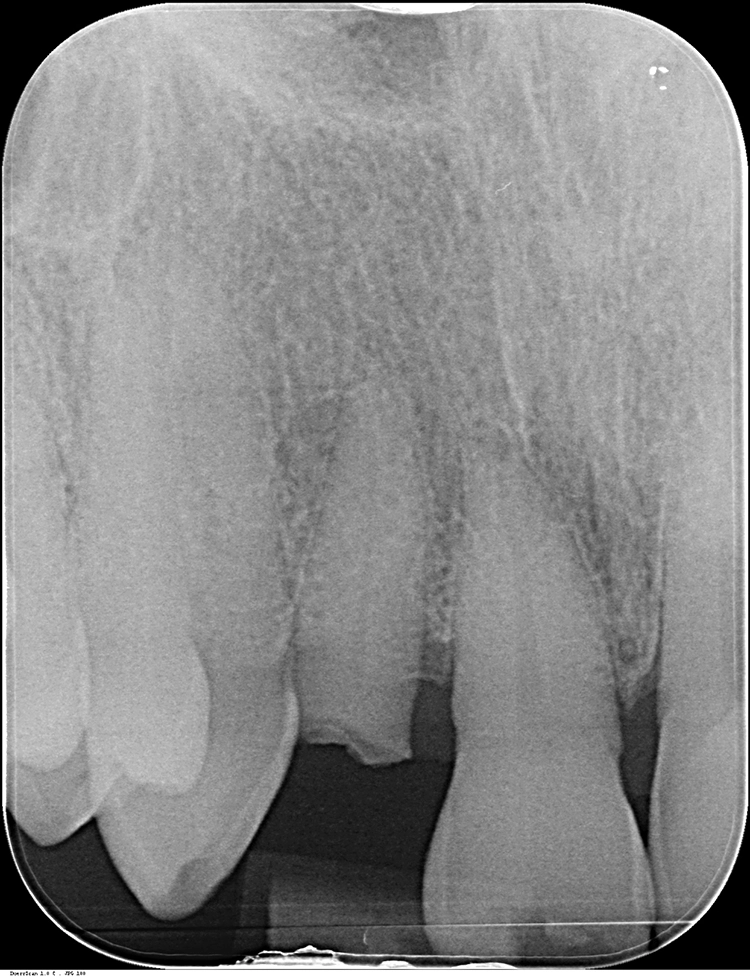

Anschließend wurde der durch die externe Resorption stark angegriffene Wurzelrest schonend entfernt. Bei der Sofortimplantation kommt es auf den Erhalt der lokalen knöchernen Bedeckung an.

Die Alveole wird von Granulationsgewebe gesäubert und direkt postoperativ durch ein Kleinröntgen auf Wurzelreste kontrolliert. Die Aufbereitung des Implantatbettes und die Implantatinsertion erfolgt im apikalen Bereich tendenziell eher palatinal. Im Bereich der Implantatschulter wurde ein Abstand von 2,5 mm zur vestibulären Lamelle eingehalten.